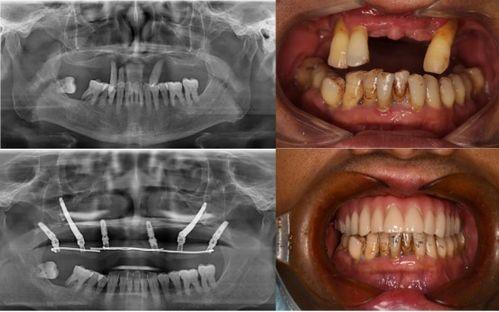

首先,讓我們來回顧一下這個事件。據網友爆料,佛山某口腔醫院在進行種植牙手術時,竟然出現了嚴重的醫療事故。視頻中,一位患者在手術過程中突然大出血,醫護人員卻顯得手忙腳亂,場面一度十分混亂。這個視頻一經曝光,立刻引起了廣大網友的關注和熱議。